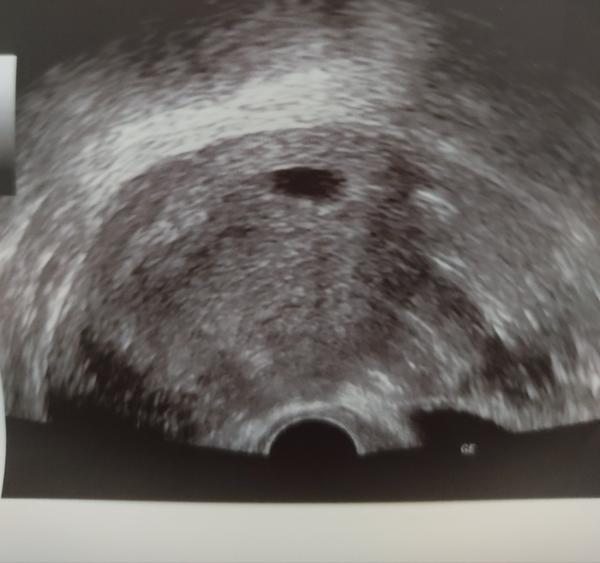

Včera som bola u dr. na potvrdenie srdiečka, žiaľ nevideli sme ani len plod. Dr. sa vyjadril, že mám prísť o 2 týždne, že som mala pravdepodobne posunutú ovuláciu. Podľa ms som v 7tt+2, ovulácia mohla byť posunutá maximálne o 2-3 dní, to viem naisto.

Podľa mňa je celkovo ten gestačny vak maličký - pred 10 dňami som bola na pohotovosti a zdal sa mi taký istý...